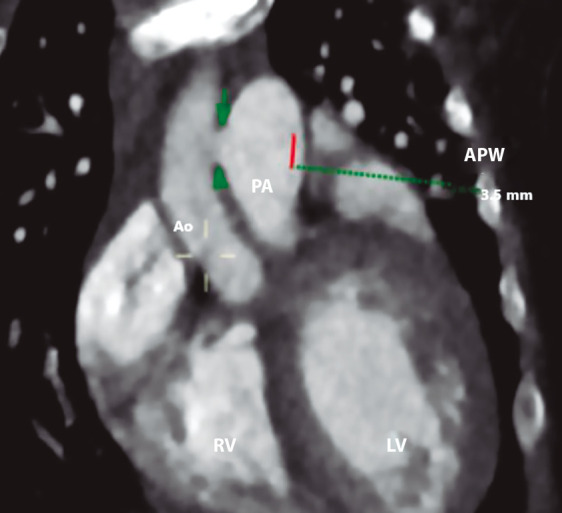

主动脉肺窗是一种罕见的先天性心脏缺陷。无其他相关异常的孤立性主动脉肺窗占所有病例的25%。手术封闭一直是,并且仍然是许多心血管中心的黄金标准。然而,经皮闭合已经成为一种可行的选择,使用各种类型的闭塞装置,根据缺损的形态、大小和边缘来选择,以尽量减少并发症,如瓣膜干扰或冠状动脉口梗阻。我们报告一例婴儿与孤立的主动脉肺窗成功治疗经皮封闭使用肌肉室间隔缺损闭塞装置,没有并发症。术后48小时患者出院。

The aortopulmonary window is a rare congenital heart defect. Isolated aortopulmonary window, without other associated anomalies, accounts for up to 25% of all cases. Surgical closure has long been, and remains, the gold standard in many cardiovascular centres. However, percutaneous closure has emerged as a viable alternative using various types of occluder devices, selected based on the morphology, size, and rims of the defect to minimise complications such as valvular interference or coronary ostial obstruction. We report the case of an infant with an isolated aortopulmonary window successfully treated with percutaneous closure using a muscular ventricular septal defect occluder device, with no complications. The patient was discharged 48 hours after the procedure.